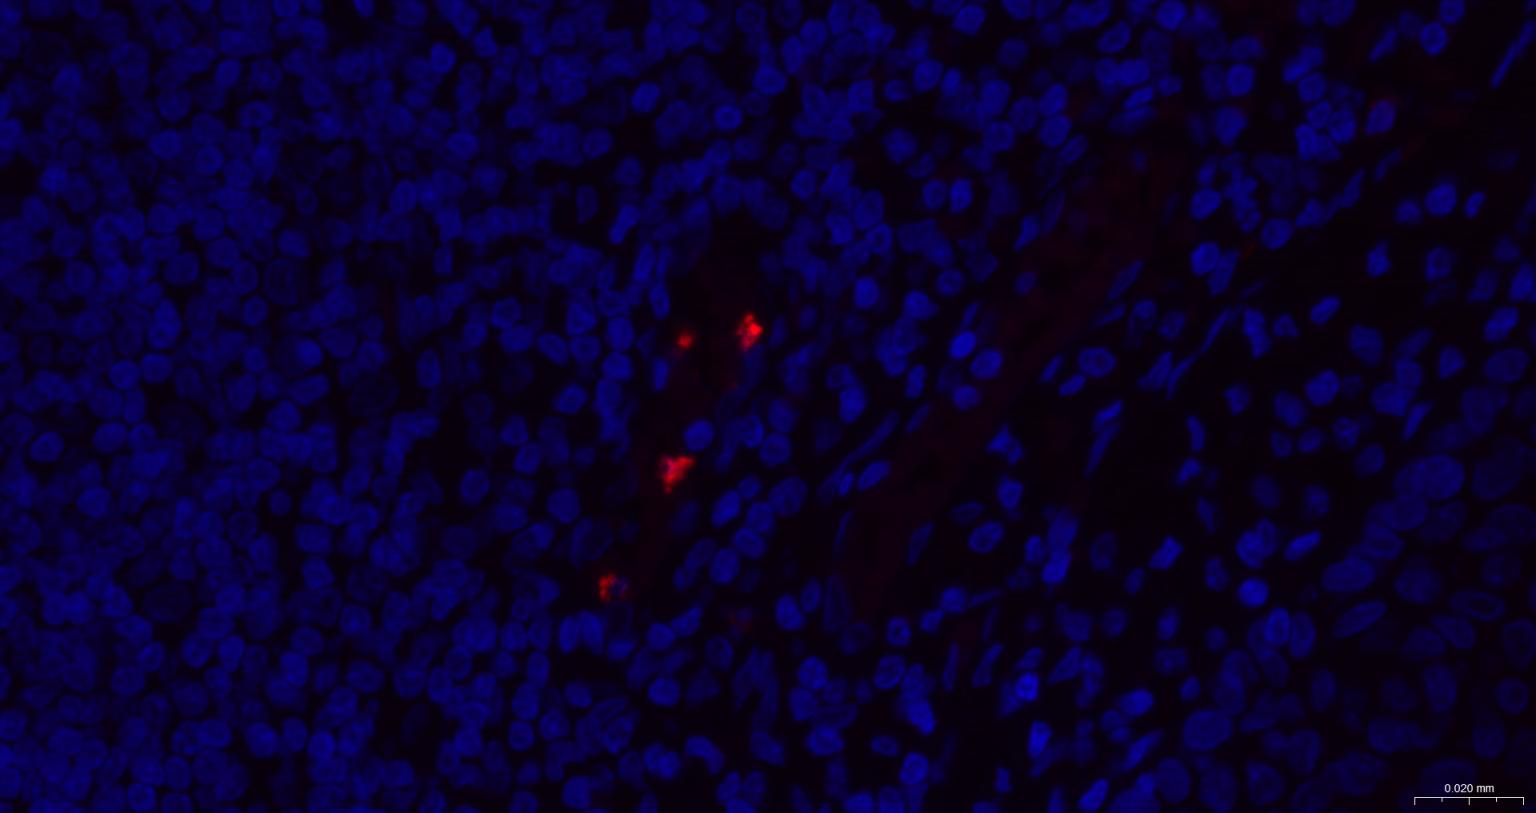

Cytolytic T lymphocytes (CTL) and natural killer (NK) cells share the remarkable ability to recognize, bind, and lyse specific target cells. They are thought to protect their host by lysing cells bearing on their surface 'nonself' antigens, usually peptides or proteins resulting from infection by intracellular pathogens. The protein encoded by this gene is crucial for the rapid induction of target cell apoptosis by CTL in cell-mediated immune response. [provided by RefSeq, Jul 2008]

| IF | Human | 1:200-1000 |